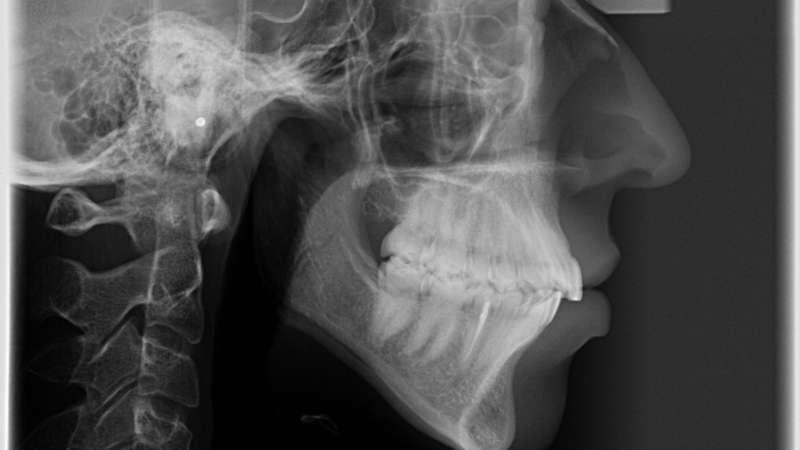

X-quang hàm chếch là một kỹ thuật hình ảnh y khoa quan trọng, giúp bác sĩ chẩn đoán và điều trị nhiều vấn đề liên quan đến vùng hàm mặt. Bài viết này sẽ giúp bạn hiểu rõ hơn về X-quang hàm chếch, từ quy trình thực hiện cho đến những lợi ích và hạn chế của nó.

Chụp X-quang hàm chếch là một phương pháp chẩn đoán hình ảnh tiên tiến, sử dụng tia X để tạo ra hình ảnh chi tiết và ba chiều của cấu trúc xương hàm, răng và các mô mềm xung quanh. Kỹ thuật này cho phép các nha sĩ có thể nhìn thấy những khu vực mà các phương pháp X-quang truyền thống như X-quang toàn cảnh hoặc X-quang cận chóp không thể hiển thị rõ ràng.

Hình ảnh từ X-quang hàm chếch cung cấp cái nhìn toàn diện về tình trạng răng miệng, giúp phát hiện các vấn đề như sâu răng, nhiễm trùng, u bướu và các dị dạng xương hàm. Phương pháp này đóng vai trò quan trọng trong việc chẩn đoán chính xác và nhanh chóng, hỗ trợ lập kế hoạch điều trị hiệu quả hơn. Với sự phát triển của công nghệ, chụp X-quang hàm chếch ngày càng trở nên an toàn hơn cho bệnh nhân, giảm thiểu tối đa mức độ phơi nhiễm tia X.